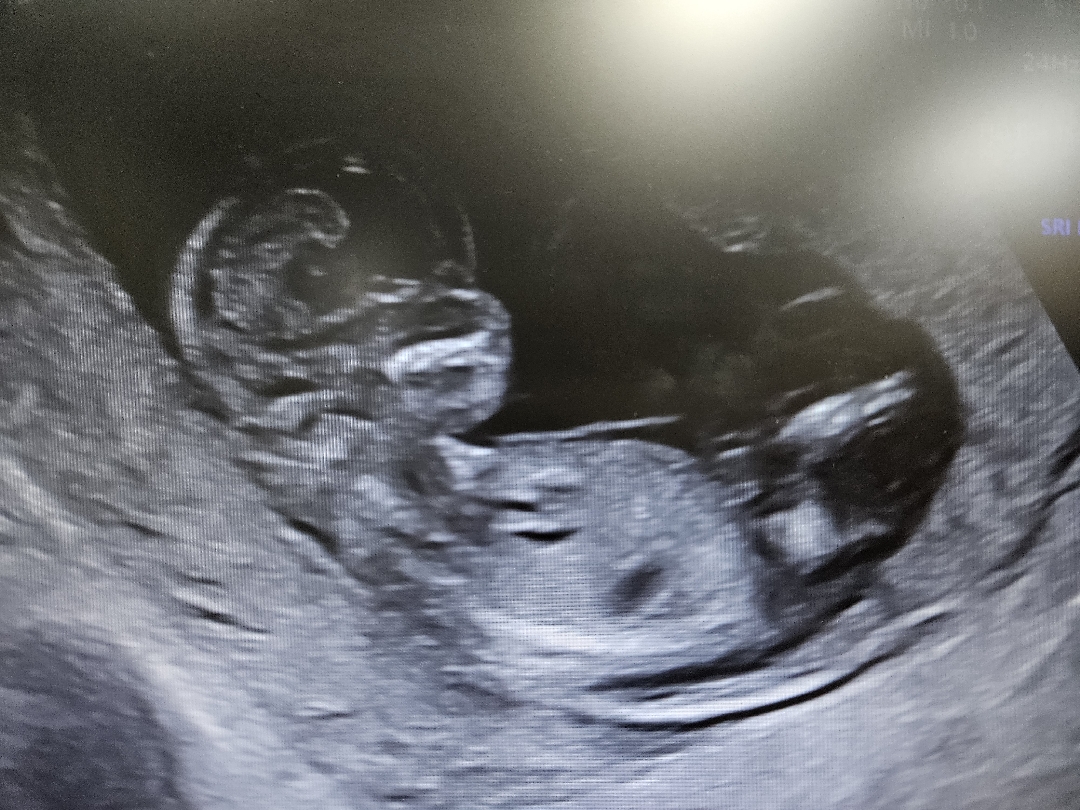

12주 각도법 봐주세요!

보이는게 맞는지 모르겠어요ㅠ

아들 한표

어느쪽 봐서 아들일까요 귱금해요ㅠ